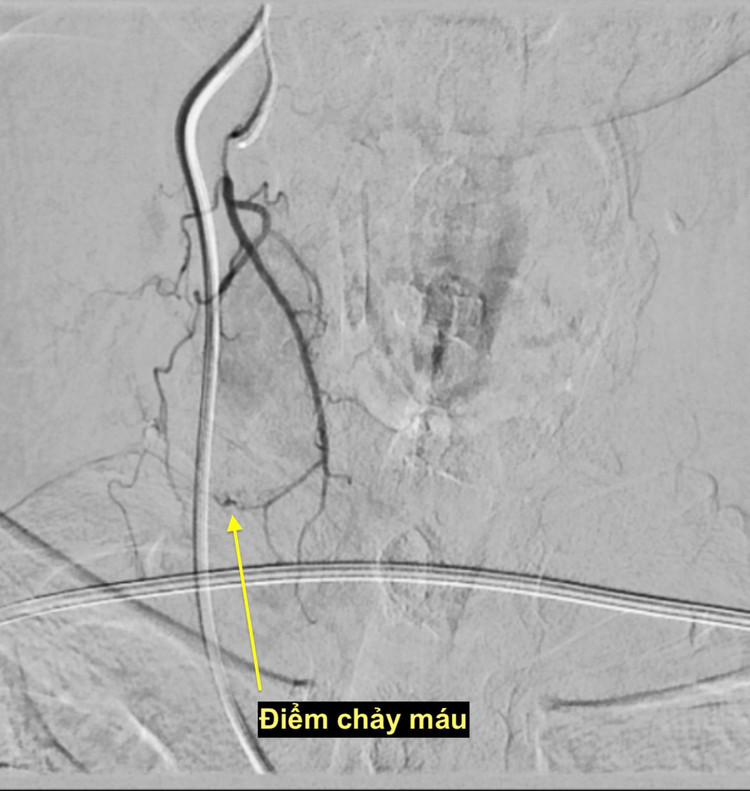

Bệnh nhân nhanh chóng được chuyển ngay sang phòng can thiệp nút mạch cầm máu. Kết quả chụp mạch cho thấy một nhánh động mạch tuyến giáp bên phải đang chảy máu. Bệnh nhân ngay lập tức được can thiệp nút mạch cầm máu, may mắn qua khỏi tình trạng nguy hiểm.

| Điểm chảy máu sau chọc tế bào tuyến giáp - Ảnh BSCC |